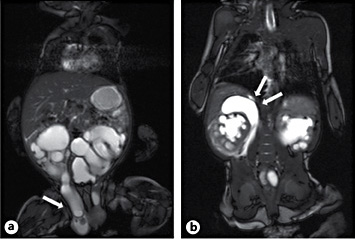

At the age of 10 weeks, surgical repair for bilateral inguinal hernia was planned within 1 month. While his baseline serum creatinine was 40 µmol/l (0.45 mg/dl), there was a sudden rise to 69 µmol/l (0.78 mg/dl). The boy showed mild discomfort, the abdomen was non-tender, the inguinal hernias appeared unchanged and were not painful. Dehydration and UTI were ruled out. Renal ultrasound showed the formally known dilation on the left side, yet hydroureteronephrosis on the right side had increased significantly. On this side, a novel fluid collection surrounding the upper pole was noted, which prompted an MRI study (fig. 1). This revealed ureteroinguinal herniation of the right megaureter. A fluid collection around the right upper pole raised suspicion of a kidney blow out. Surgical exploration was conducted on the same day.

MRI showing ureteral herniation (a; arrow); b pararenal fluid collection, suspicious for kidney blow out (arrows).